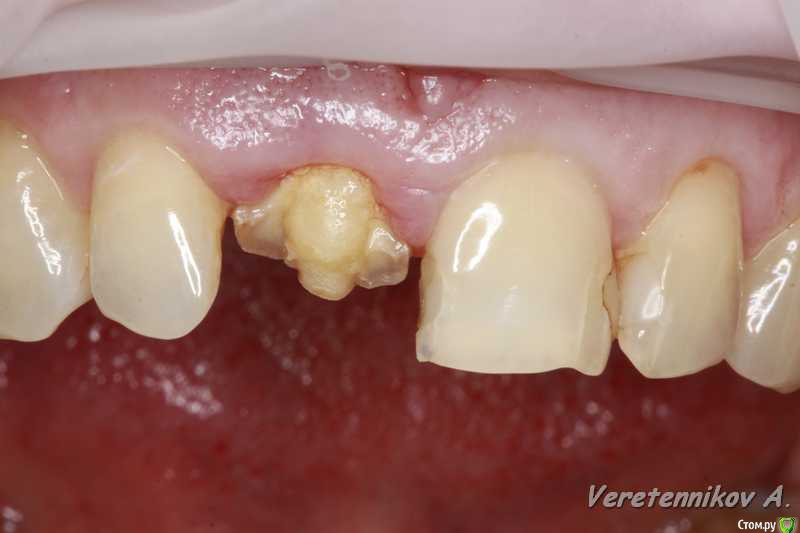

Популярный пост an_ver Опубликовано 15 января, 2016 Популярный пост Поделиться Опубликовано 15 января, 2016 11,жил долго и счастливо..но тут Новый год(((, скол ниже уровня ЦЭС на 3 мм...от экструзии отказалась.Из своего зуба сколхозил шаблон,чтоб наверняка. Удалил,кюретаж,вестибулярка целая, SPI 4.2*13 мм,с бугра ССТ,на всякий)),в щели Апатос,врем.абатмент,врем.коронка из своего зуба. 1ч.20мин.)) 27 Ссылка на комментарий

k.t.m. Опубликовано 15 января, 2016 Поделиться Опубликовано 15 января, 2016 в щели апатос,сст в сформированный карман! Андрей красиво и все по пунктам,как так вышло что сосочек порвался?может не стоило так глубоко сст заводить? 1 Ссылка на комментарий

an_ver Опубликовано 16 января, 2016 Автор Поделиться Опубликовано 16 января, 2016 (изменено) в щели апатос,сст в сформированный карман! Андрей красиво и все по пунктам,как так вышло что сосочек порвался?может не стоило так глубоко сст заводить?Чесно,фиг знает((( тока счас обратил внимание,наверно 15С орудовал глубоко (набор Деплер для туннеля в клаве был),((( немного лоскут перфорнул...если кто заметил,решил глубже завести ластик сст Изменено 16 января, 2016 пользователем an_ver Ссылка на комментарий

an_ver Опубликовано 16 января, 2016 Автор Поделиться Опубликовано 16 января, 2016 Клёво!!!Можно вопрос: как сст всовывали ?Просто опыта в этом аспекте очень мало и понятие "в щели" не совсем понятно.СпасибоВ щели: это свободные обьем лунки,после установки импланта,т.е. все пустоту забиваем графтом (Апатос). По ССТ: скальпель 15С, параллельно кости осторожно,маятниковыми движениями,до уровня прикрепления или глубже формируете карман,вкол с вестибулярки-выкол в лунке,вкол в сст,выкол там же,далее вкол внутри кармана и затягиваете сст...но проще посмотреть...сейчас А.Смолякова по рецессии выложила видео,принцип такой же 2 Ссылка на комментарий

k.t.m. Опубликовано 16 января, 2016 Поделиться Опубликовано 16 января, 2016 перфо не заметил,но понял теперь почему так глубоко сст!ждем динамики! Ссылка на комментарий